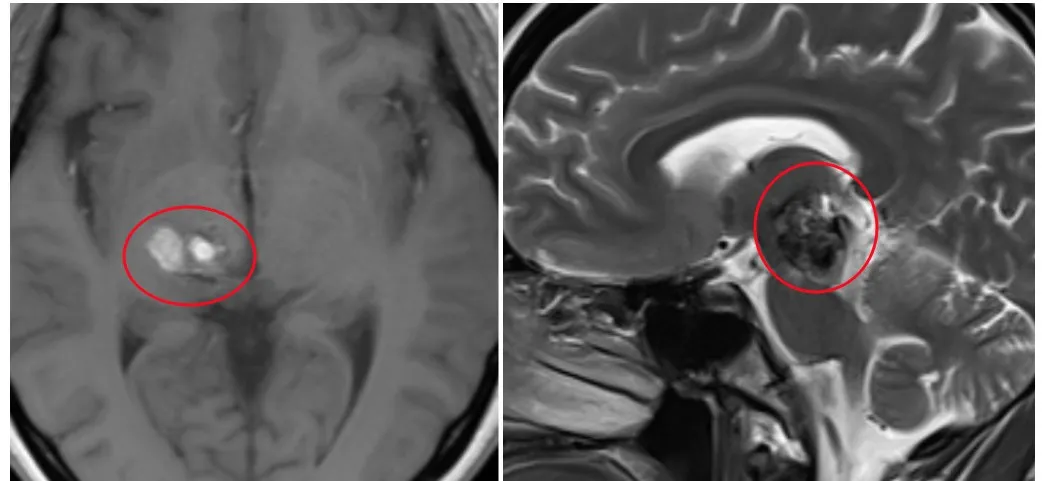

由于思睿多年多年的出血性病变,中脑右侧有明显的轴内出血,延伸至丘脑,出现神经功能受,且血管畸形粘连严重,剥离难度极大。在术前巴教授,巴教授认真的研析了思睿的影像学的资料,了解病变的前后、左右的比邻关系,做到完全的了解病变的特性,才能做到手术中游刃有余。

2024年6月4日,在国内神经外科医生辅助配合,神经电生理监测下,思睿的丘脑-中脑海绵状血管瘤手术平稳进入到颅内切除的部分。为了精准切除病灶的同时,还进行了术中神经电生理监测,最后为思睿全切病灶。